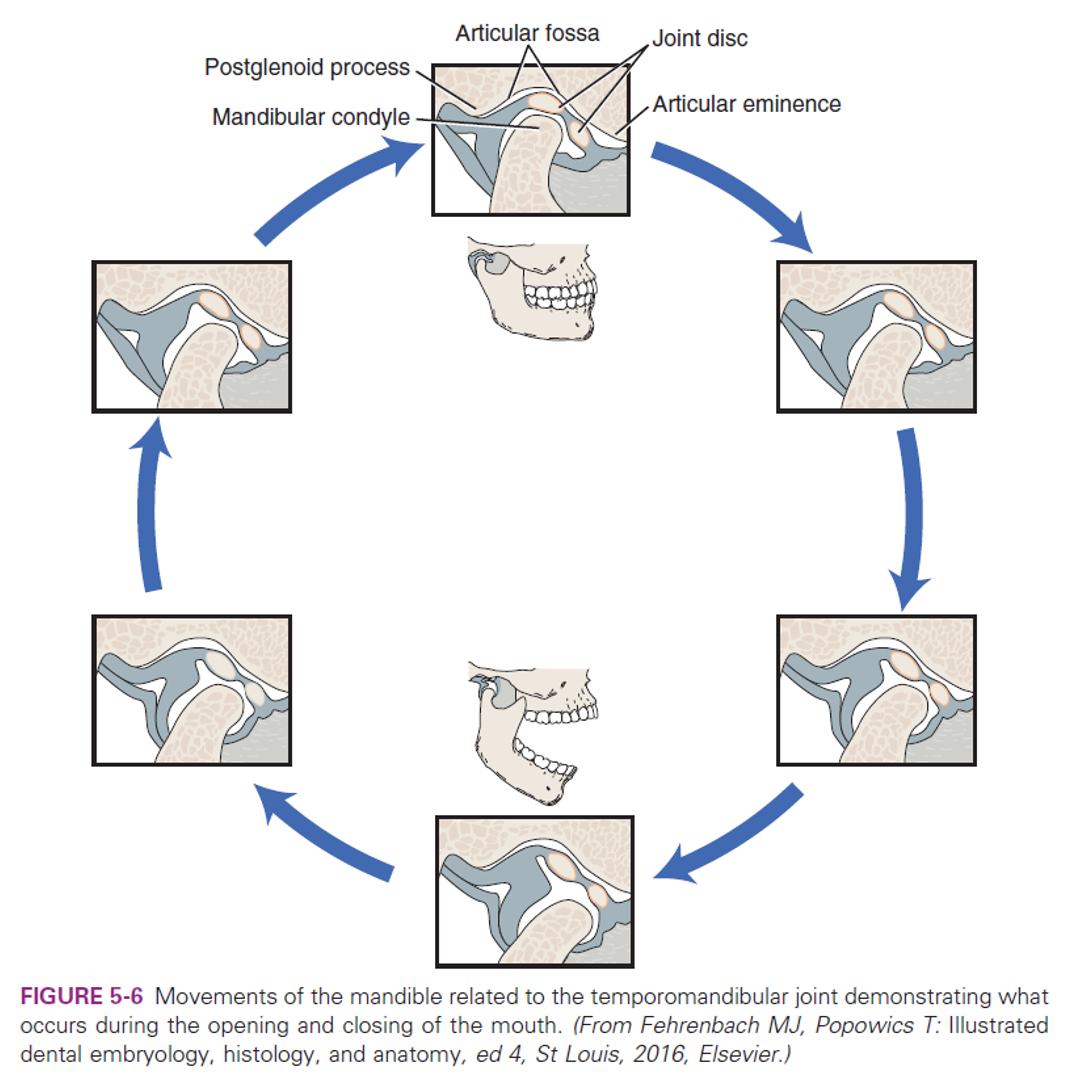

JAW movement

- 旋轉: 下顎離上門牙2.5cm

- 平移: disc-condyle complex 沿 articular eminence 滑動,可再往前張開約 1.5 公分

movement